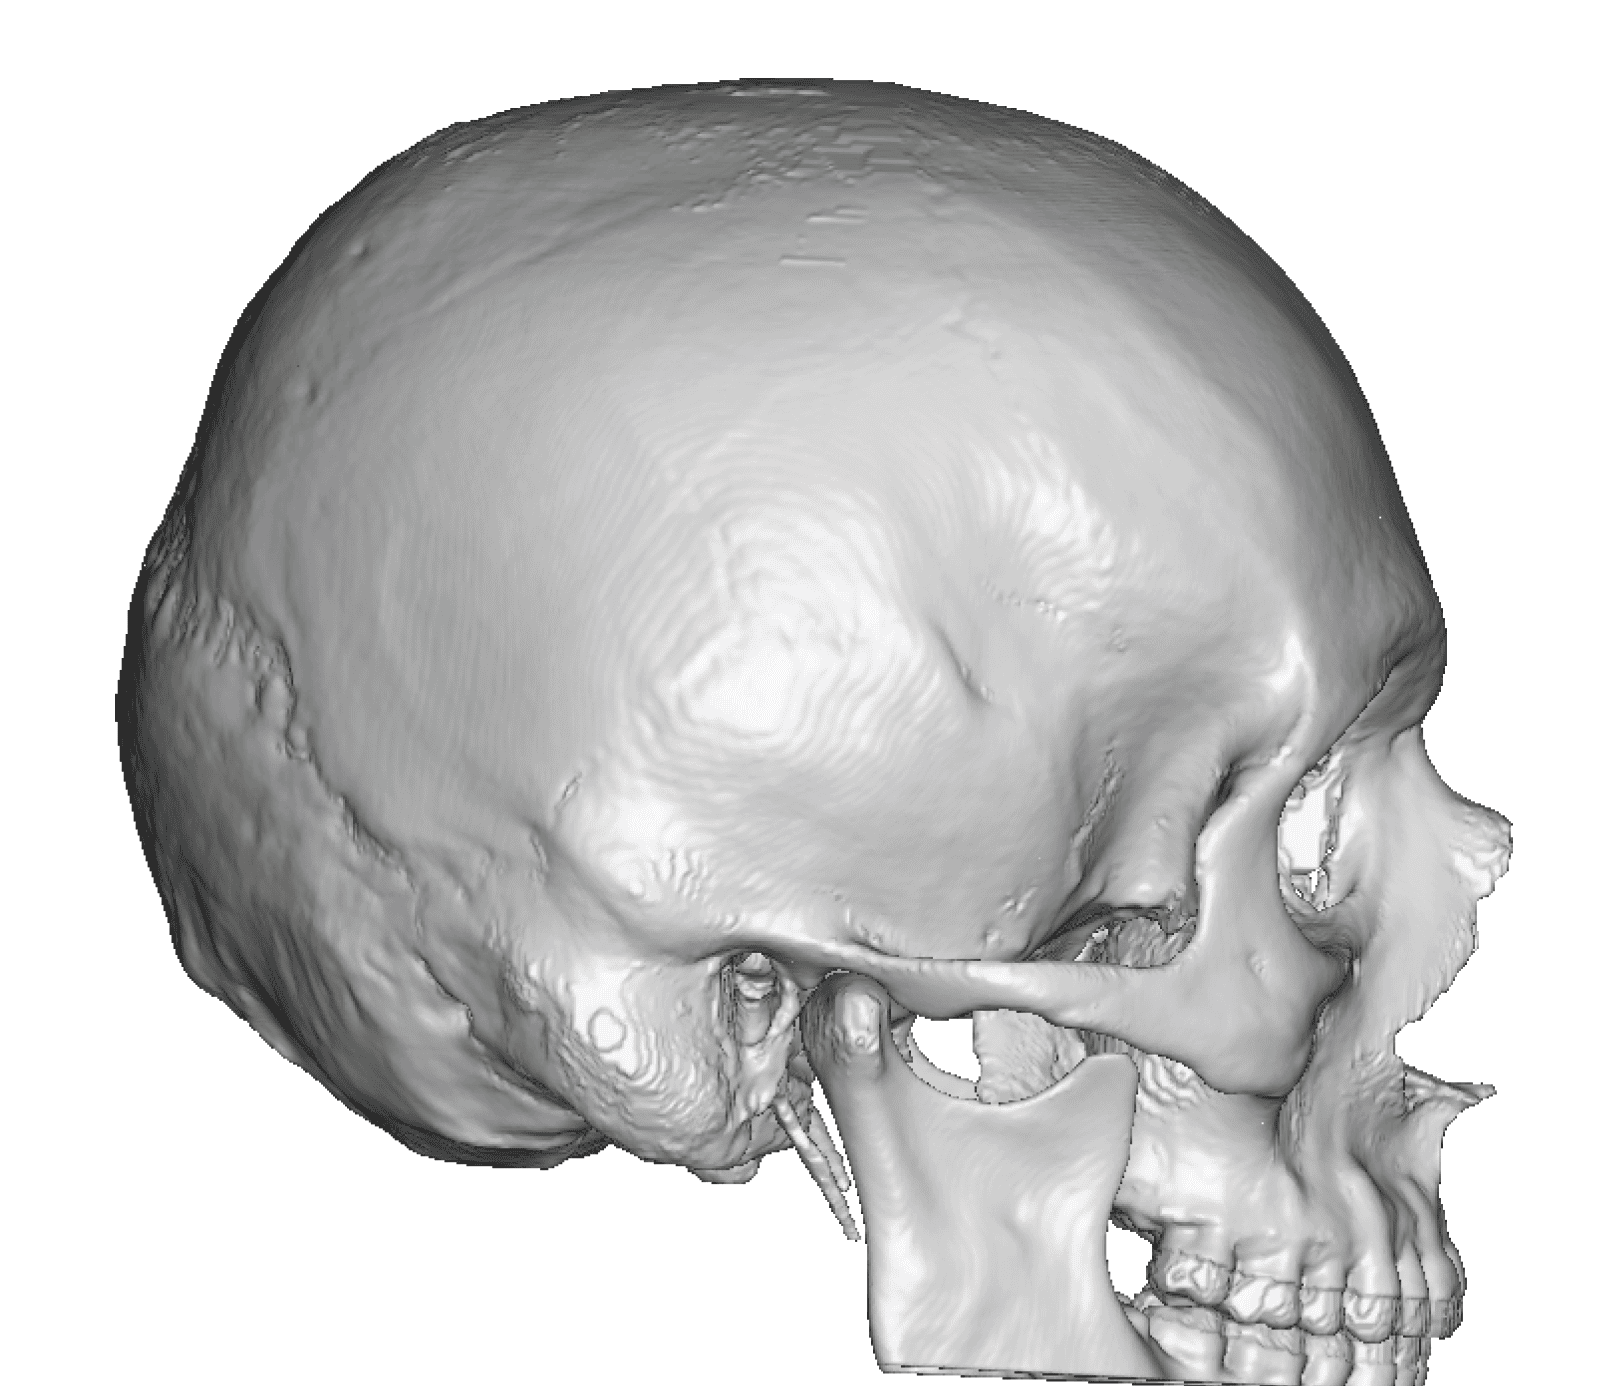

Patient 28

Desire for rounder shape to the top of the head from a congenital parasagittal deficiency skull shape.

Custom skull implant designed to fill in the parasagittal deficiencies.

Desire for rounder shape to the top of the head from a congenital parasagittal deficiency skull shape.

Custom skull implant designed to fill in the parasagittal deficiencies.